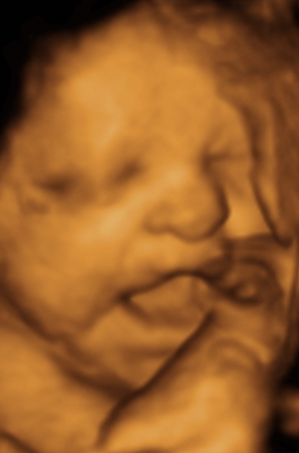

Week 33 Photos

No matter if you’re 6 weeks or 42 weeks, we’ve got the right tools and expertise to make every ultrasound special. Your baby’s first show - front-row seats for 15 of your closest loved ones!

Your baby now weighs about 4 1/3 pounds and measures 17 1/4 inches long (the size of a pineapple). To measure the frequency of your baby's movements and overall wellbeing, your doctor may recommend a test called a Biophysical Profile.